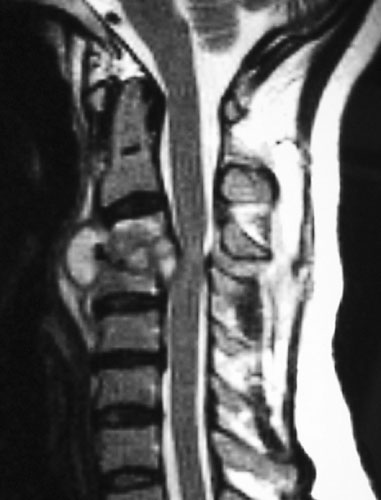

Craniovertebral Junction Anomaly

The junction of the skull with the neck is called craniovertebral junction. This is the site for a number of pathologies, that can have severe neurological problems and can be potentially life threatening. Diagnosis is achieved by CT and MRI, and treatment involves decompression and provision of stability by metallic implants.